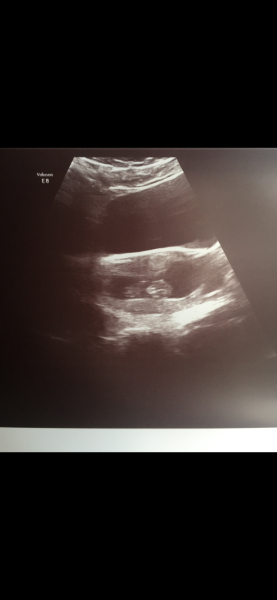

I also have a tilted uterus and found some scan photos turned out better than others! Like previous comments have mentioned I think it depends on the machine quality etc... With our DS we went for a couple of early private scans both were performed abdominally.... I will attached a photo below, I believe I was around the 9 week mark here ✨ keep in mind that this was 6 years ago!

We laughed and said he looked like a little gummy bear with his hands by his head 🤣